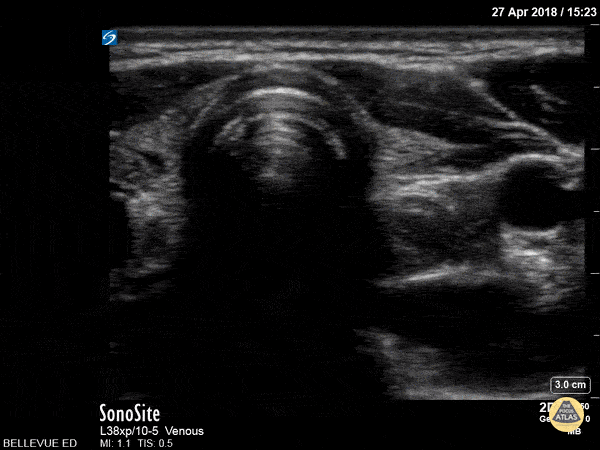

In the center of the screen we see the trachea in transverse view with its round hyperechoic cartilaginous rings. To the right of the trachea is the smaller, collapsed, muscular walled esophagus which moves as the patient swallows in this clip. We can also see the pulsatile carotid arteries bilaterally at the edges of the screen.